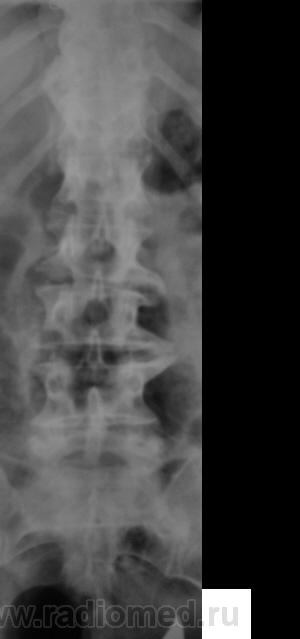

Спондилолистез L5-S1 - истинный, поэтому природа сама набедокуривши, сама и оберегает. Трудно представить безсимптомное течение, если бы это было последствием травмы. Очень рад, что Андрей Юрьевич приводит выдержки из Рейнберга. Судя по желтизне страниц - это первое издание.

По данному случаю:на мой взгляд, он является примером того, что попытки обяснить клинику(страдания пациента) только изменениями на R-граммах несостоятельны (если бы, у пациентки были жалобы,скажем на боли в области поясницы, сделали бы вывод-"что вы хотите?!-деформирующий спондилёз, да ещё спондилолистез- из-за этого и болит"). Думаю, многие сталкивались такими направлениями: "Направляеться на R-графию пояснично-крестцового отдела позвоночника.D.S.:Исключить остеохондроз ".